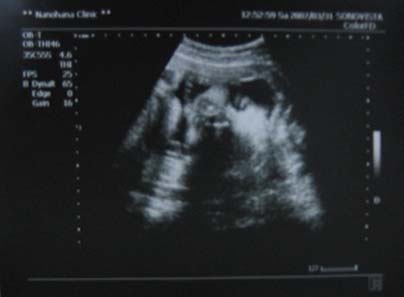

31日に撮ったエコーでは、ベビちゃんが顔を見せてくれました!

わかります??

まあ、亡霊写真のようにも見えてしまうんですが、なんとなく顔。です。

最近わかってきましたが、I先生が今のところ一番エコーうつすのがうまいです。